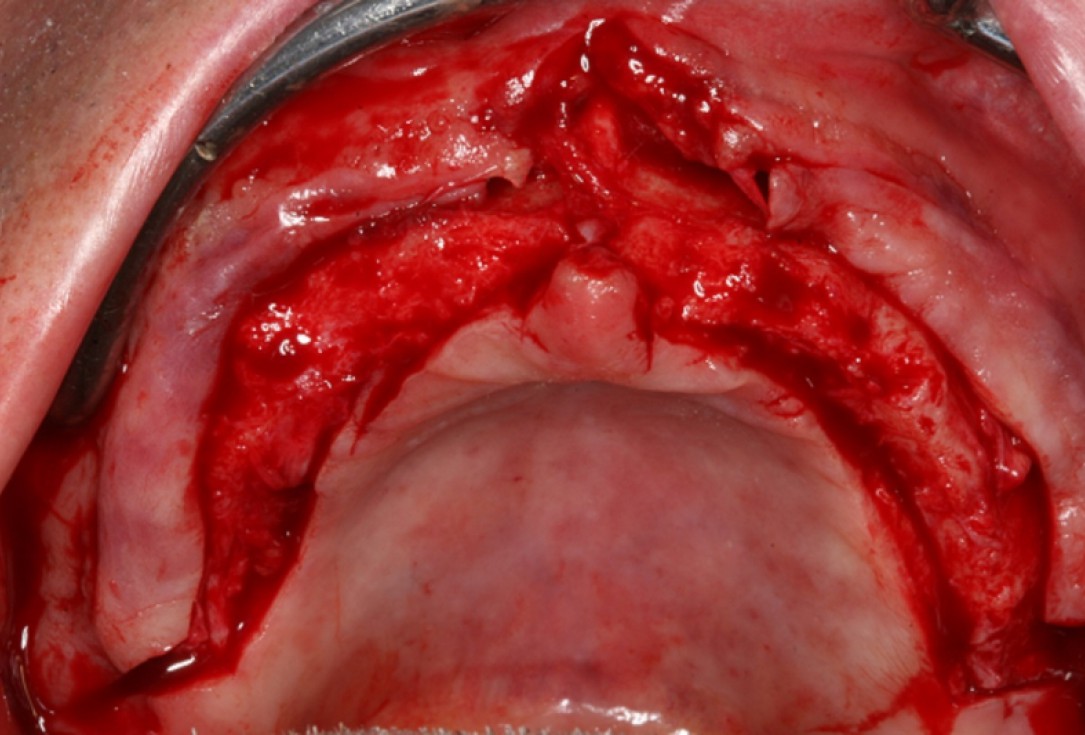

01/10 - Surgical presentation of the alveolar ridge with reduced amount of horizontal bone availableCircular bone splitting with maxresorb® & collprotect® membrane - PD Dr. J. Neugebauer

Surgical presentation of the alveolar ridge with reduced amount of horizontal bone available